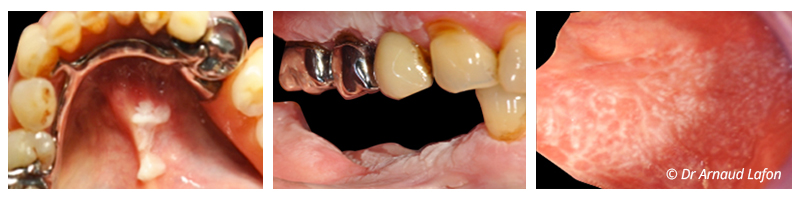

Fig. 01 : les lésions de la muqueuse orale à potentiel malin les plus fréquentes. Dans l’ordre de gauche à droite : leucoplasie orale, lésions lichénoïdes buccales, lichen buccal.